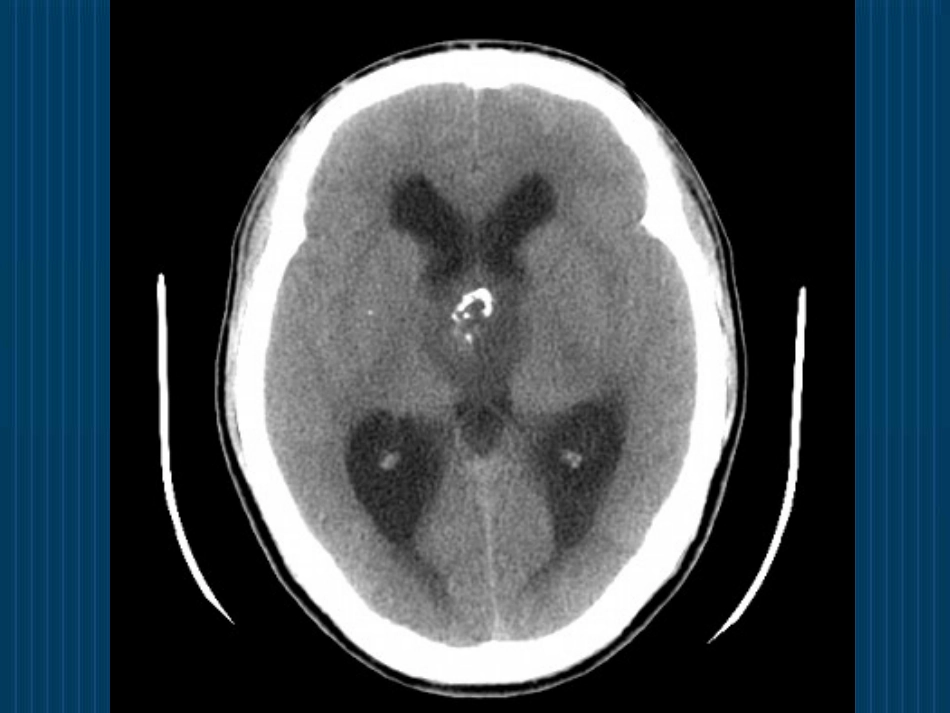

怎样看头颅CT与MRI?八里庄第二社区卫生服务中心康复科kingakun@126.com2011年03月31日问题1、什么样的片子是CT?什么样的片子是MRI?问题2、头颅CT与MRI是怎么拍出来的?CT是怎么拍出来的?•CT(Computerizedtomography)•原理:X线束透过人体不同密度的组织被吸收的量大小不同,投影到探测器上,转换为数字信号,经电脑处理而获得图像。•黑影——低密度区,如脑室;•白影——高密度区,如骨骼;•组织对X线的吸收系数称为——CT值•水的CT值——0HU•骨骼的CT值——+1000HU•空气的CT值——-1000HUMRI是怎么拍出来的?•MRI(Magneticresonanceimaging)•原理:发射特定频率的射频脉冲激发H原子核,作为小磁体的H原子核可以从射频脉冲中获取能量产生共振,停止发射射频脉冲后,H原子核所吸收的能量逐渐释放,恢复至原来的状态,这个过程所需要的时间有两种,一种是纵向弛豫时间(T1),一种是横向弛豫时间(T2)。由于人体的组织均含有H2O和C-H结构,信号强度与H原子核的密度有关,故不同组织有其各自的T1和T2,被探测器所获得,经电脑程序处理形成图像。问题3、怎么看CT?基本信息•1、是否为CT片;•2、分清左右;•3、患者姓名;•4、拍片时间;•5、找病灶……正常头颅CT眦耳线,层厚8-10mm常见疾病的CT诊断•大面积脑梗死常见疾病的CT诊断•基底节区脑梗死常见疾病的CT诊断•脑出血常见疾病的CT诊断•脑干出血常见疾病的CT诊断•颅内肿瘤问题4、怎么看MRI?基本信息•1、是否为MRI片;•2、分清T1、T2;•3、患者姓名;•4、拍片时间;•5、找病灶……常见疾病的MRI诊断•略……